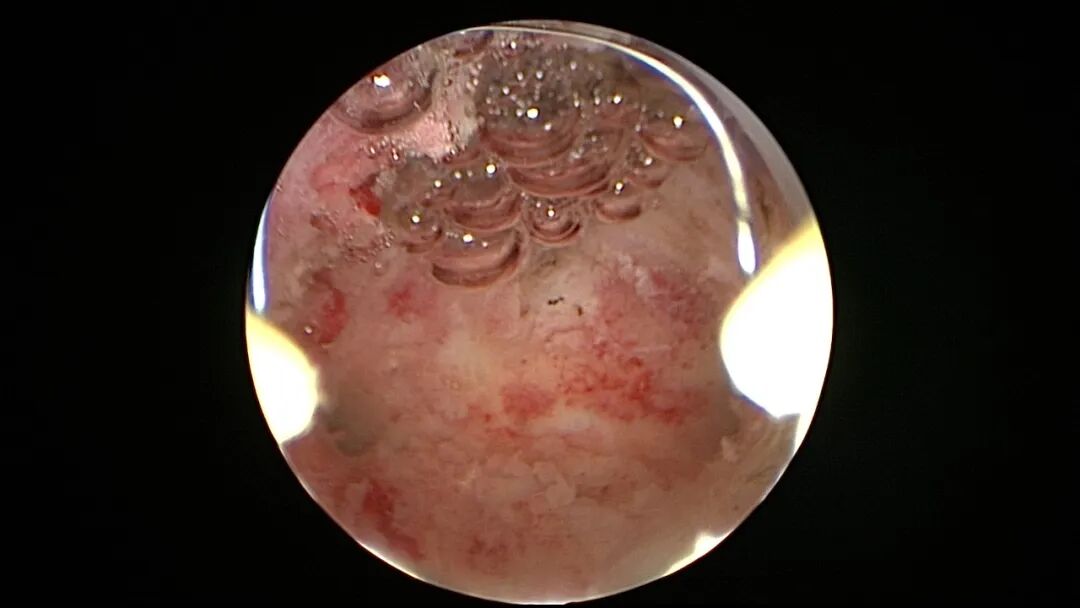

第七次宫腔镜:2025年6月因异常子宫出血、月经淋漓不净10+天,行宫腔镜探查,宫颈管见陈旧血丝,宫腔形态欠规则,宫腔两侧纤维性粘连,宫腔狭小,内膜薄,内膜充血。单极电针分粘,宫腔形态基本恢复正常,左侧输卵管开口显露,右侧输卵管开口不可见。内膜病检为增殖期样子宫内膜伴出血。

第八次宫腔镜:2025年7月宫腔镜二探取球囊,宫腔形态正常,双侧输卵管开口可见,内膜薄,片状充血。球囊在宫腔具有持续塑形作用,分粘术中没有显露的右侧输卵管开口已自我修复。